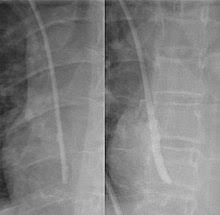

What are central venous catheters? Central venous catheters are helpful for taking care of your child; Indications for central line (central venous catheter) insertion. Central venous catheters(cvcs) are often required to establish venous access in critically ill patients in order to administer rapid fluid resuscitation, blood products, and vasopressors. A central venous catheter is a tube that goes into a vein in your arm or chest and ends at the right side of your heart (right atrium). Central venous catheterization is widely used as a vehicle for rapid volume resuscitation. These are implemented at catheter insertion and for the duration of its use. The internal jugular is usually preferred to subclavian approach where possible as it is less likely to lead to pneumothorax. Internal jugular (ij), subclavian, and femoral. Placement of larger catheters in more centrally located veins is often needed in critically ill patients. However, they can increase the risk of infections when bacteria grow in the catheter and travel to the bloodstream. The physician who is inserting the catheter will make two small incisions on your chest. While cvcs are not considered the best access option and are generally avoided when possible, patients unable to immediately get a fistula or graft, or if their fistula or graft are in the process of healing, may need for a temporary access.

It's also called a central venous line or central line. It may be inserted through a vein in the neck, chest or arm. What are central venous catheters? It ends in 1 of the venae cavae just before entering the right atrium. Central venous catheters (cvc) or lines (cvl) refer to a wide range of central venous access devices but can broadly be divided into four categories. Several strategies can reduce central venous catheter related morbidity; The physician who is inserting the catheter will make two small incisions on your chest. A central venous catheter (katheter), also known as a central line or cvc, is long, soft, thin, hollow tube that is placed into a large vein (blood vessel).

These are implemented at catheter insertion and for the duration of its use. Peripherally inserted central catheters (piccs) and nontunneled central venous catheters (cvcs) are indispensable in current medical practice, with both serving central venous access needs. The pressure monitoring assembly is attached to the. It ends in 1 of the venae cavae just before entering the right atrium. To streamline patient care, our arrow® cvcs are now available with pressure injection capabilities; It is acquired by threading a central it is threaded so that the tip of the catheter rests in the lower third of the superior vena cava. If the catheter is in your chest, sometimes it is attached to a device called a port that will be under your skin. Cancer treatment usually includes a variety of injections, blood draws, and intravenous medications and fluids. A central venous catheter (cvc) is a thin, flexible tube (catheter) that is placed into a large vein above the heart. This is called a central line associated blood stream infection or clabsi. The jugular veins are one of the most popular site. A clabsi can be serious and life threatening. Central venous catheters are helpful for taking care of your child;